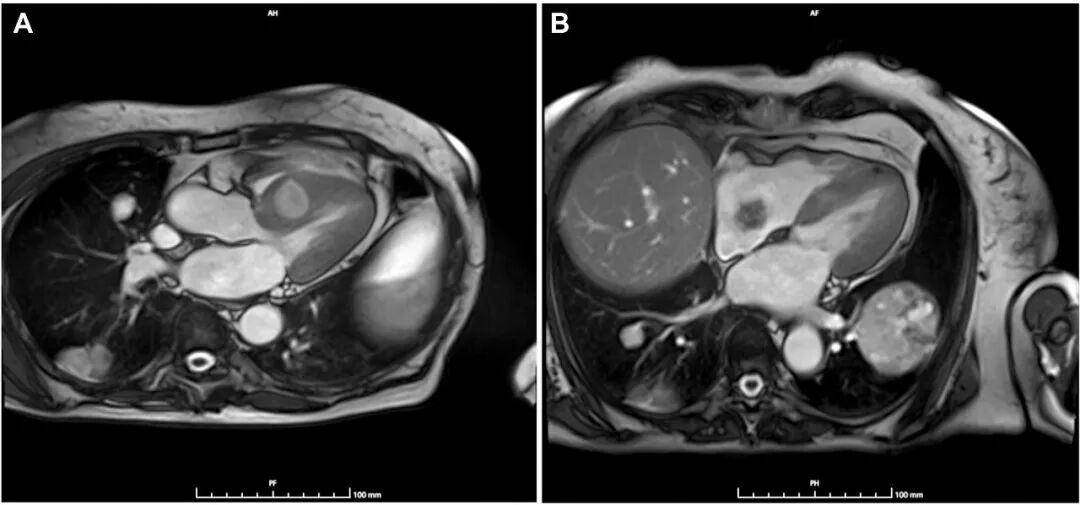

全身CT扫描显示,与2023年CT扫描相比,双侧多发性肺部肿块大小进一步增加(左侧最大者7.2 cm对比6.2 cm),边缘清晰,内部可见粗糙的血管结构和坏死液化灶(图2)。未检测到额外结节。在奇异食管凹陷处报告的部分实心结节为实心圆润,测量为11毫米(对比9毫米)。证据显示右上肺叶和同侧下肺叶需进行楔形切除。检查未发现其他器官有其他病变。心脏磁共振显示室间隔中段基底部有一大肿块(最大尺寸,5×35cm)(图3A)。对比剂注射后序列显示不规则晚期钆增强,提示右心房存在一个通过细长蒂附着的肿块(最大尺寸,2.5×3cm)(图3B),该肿块在对比剂注射后序列中未见晚期钆增强。

图3. A 心脏磁共振显示室间隔中段基底部水平有一肿块(尺寸,5×35cm)。B 四腔心切面显示一活动性新生物,通过蒂附着于右心房游离壁。